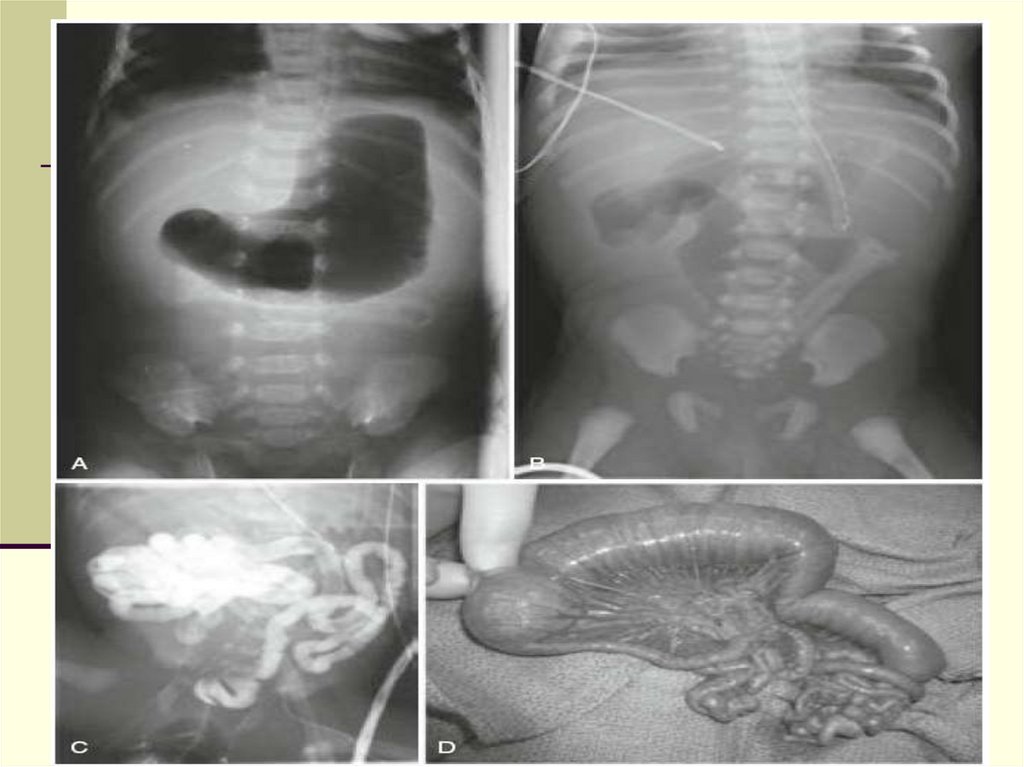

26. Диагноз

Обзорная рентгенография

Несколько расширенных петель с округлыми

образованиями в просвете

Отсутствие уровней

Кальцинаты в брюшной полости

Ирригография

Микроколон

27. Консервативное лечение неосложненного мекониевого илеуса

4) Контрастная клизма с гастрографином или урографином

(гиперосмолярный раствор)

NB! Контраст должен проходить в расширенные петли кишечника